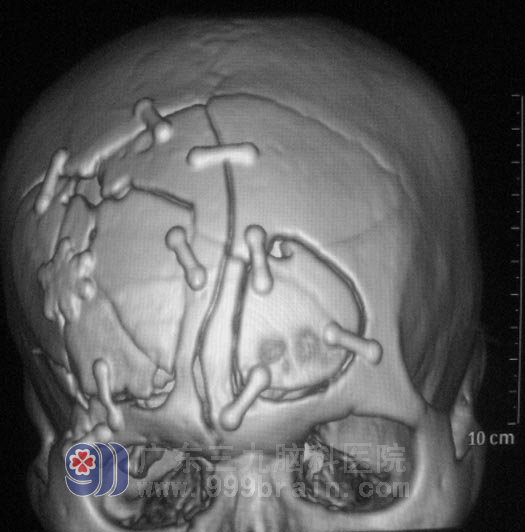

▲粉碎性骨折整复术后

由鲁明主任主刀在全麻下行右侧前颅窝底修补术+右侧额叶脑内血肿、坏死组织清除+双侧额部跨窦硬膜外血肿清除+右侧额颞、左侧额部粉碎性骨折整复术+左侧桡骨中段骨折切开复位钢板内固定+左侧桡神经探查术。术中见额骨中部线形骨折,起自左侧额窦沿中线先后至冠状缝处,右侧额颞骨交界处凹陷性骨折及血肿;硬膜外血肿及右侧额叶硬脑膜破裂,脑组织挫伤伴陈旧性血肿,沿硬脑膜破裂处放射性扩大硬膜。手术经过顺利。经过两周的康复治疗,阿明恢复满意已办理出院。